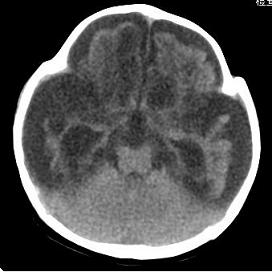

男,4个月大,2个月前无诱因下四肢抽搐、伴呕吐,近2天来抽搐频发,伴发热。查体:双眼疑视,神萎、纳差;颈抵抗,四肢张力高。

病史太长了,原因不好定,不过如果2个月前小儿正常的话可考虑积水型无脑畸形,积水型无脑畸形小儿刚生下来表现可正常,存活一两个月后出现症状.

另不除外缺血缺氧性脑病,感染等改变

2个月前缺血缺氧性脑病留下的后遗症。

脑出血后,软化灶形成了。脑发育不良

支持缺血缺氧性脑病留下的后遗改变(脑软化灶+脑发育不全+双侧慢性硬膜下积液+小头畸形)。

要注意化脓性脑膜、脑炎,硬膜下积脓,脑积水的可能,建议腰穿助诊。